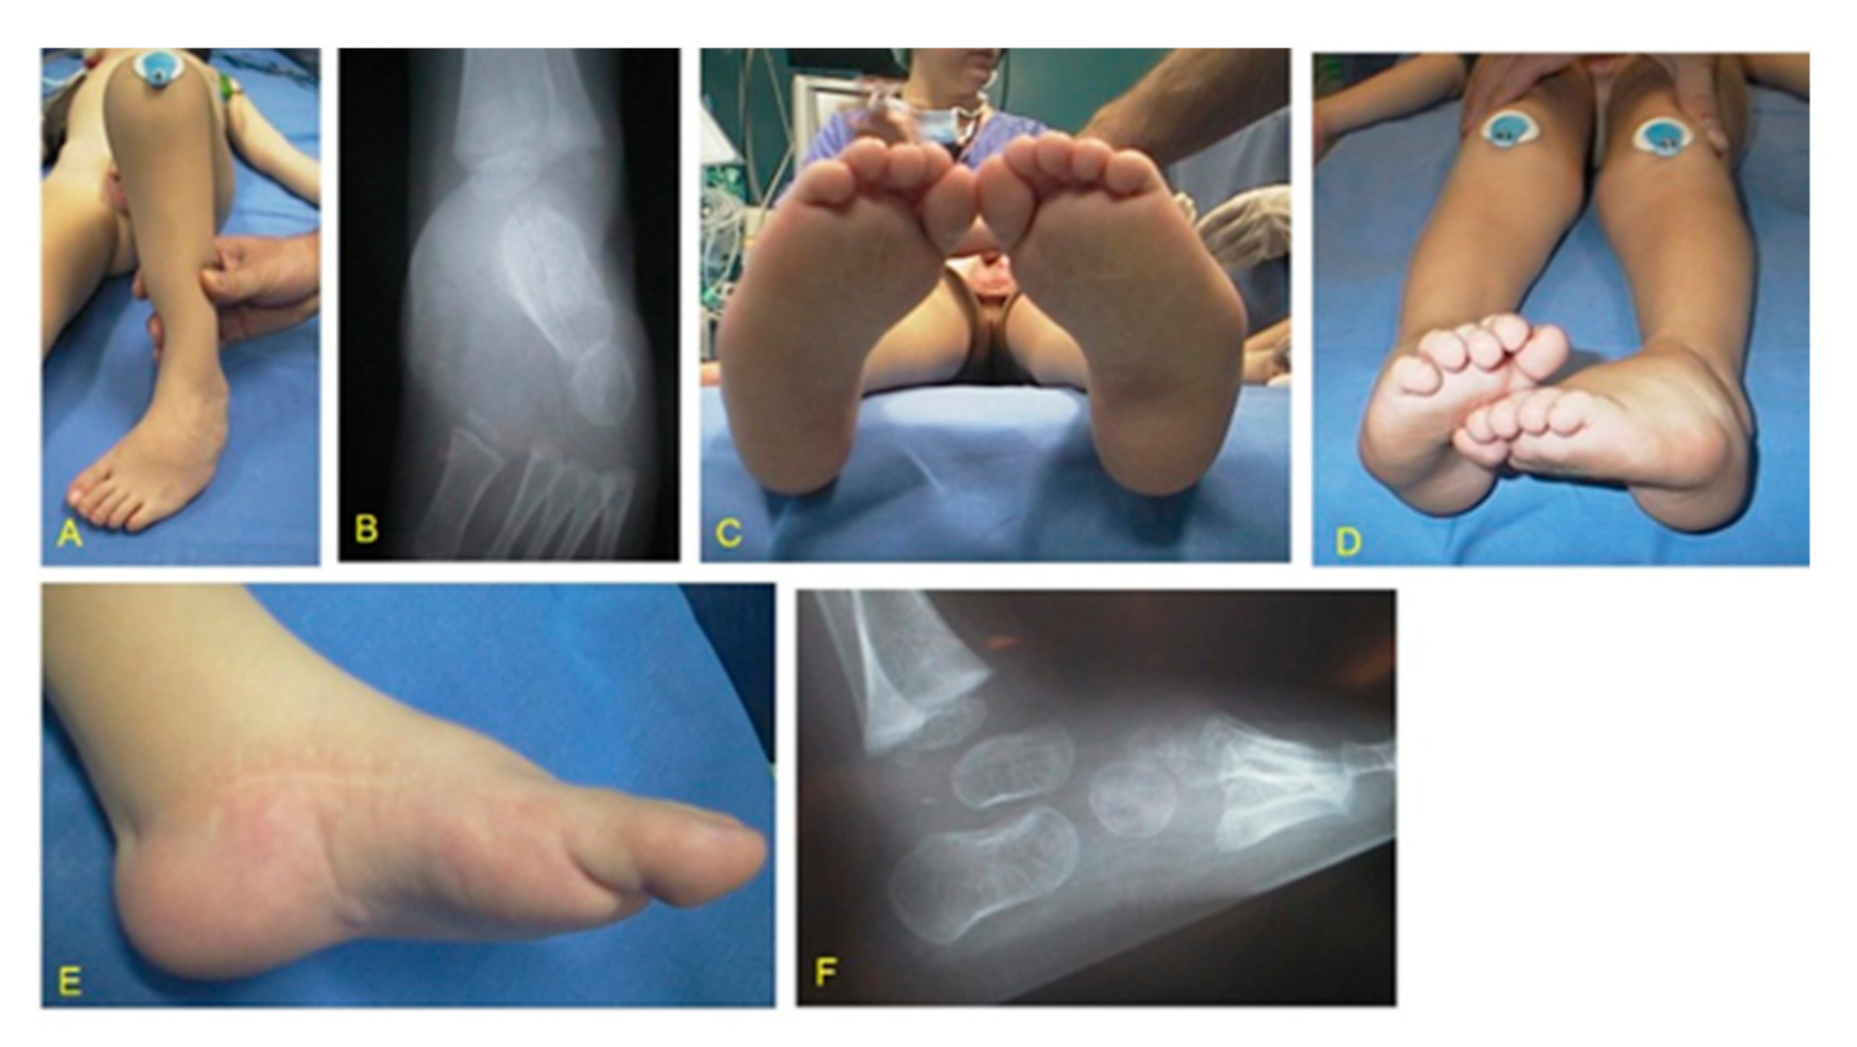

Figure 2. MS (Moebius syndrome) patient with unilateral severe CF (clubfoot) right: (A) clinical aspects at birth; (B) medial aspect at the time of peritalar release at the age of 7 months showing a rigid equinus, deep crease above the heel, and a transverse crease in the sole; (C) lateral aspect with typical skin excess; (D) medio-plantar crease; (E) postoperative result after peritalar release; (F) postoperative plantar aspect.